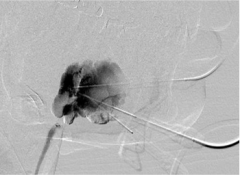

• [背景] 上消化道出血栓塞治疗的背景因素 日期:2025-12-16 20:37:02 点击:125

出血病人外科治疗有较高的死亡率和并发症发生率。 消化道出血的栓塞已经是一个成熟的技术 但是,专家和相关设备并不是哪儿都有 相关指南完全缺乏 需要讨论的包括 适应症 血管造影技术 栓塞技术 栓塞的结果和并发症...